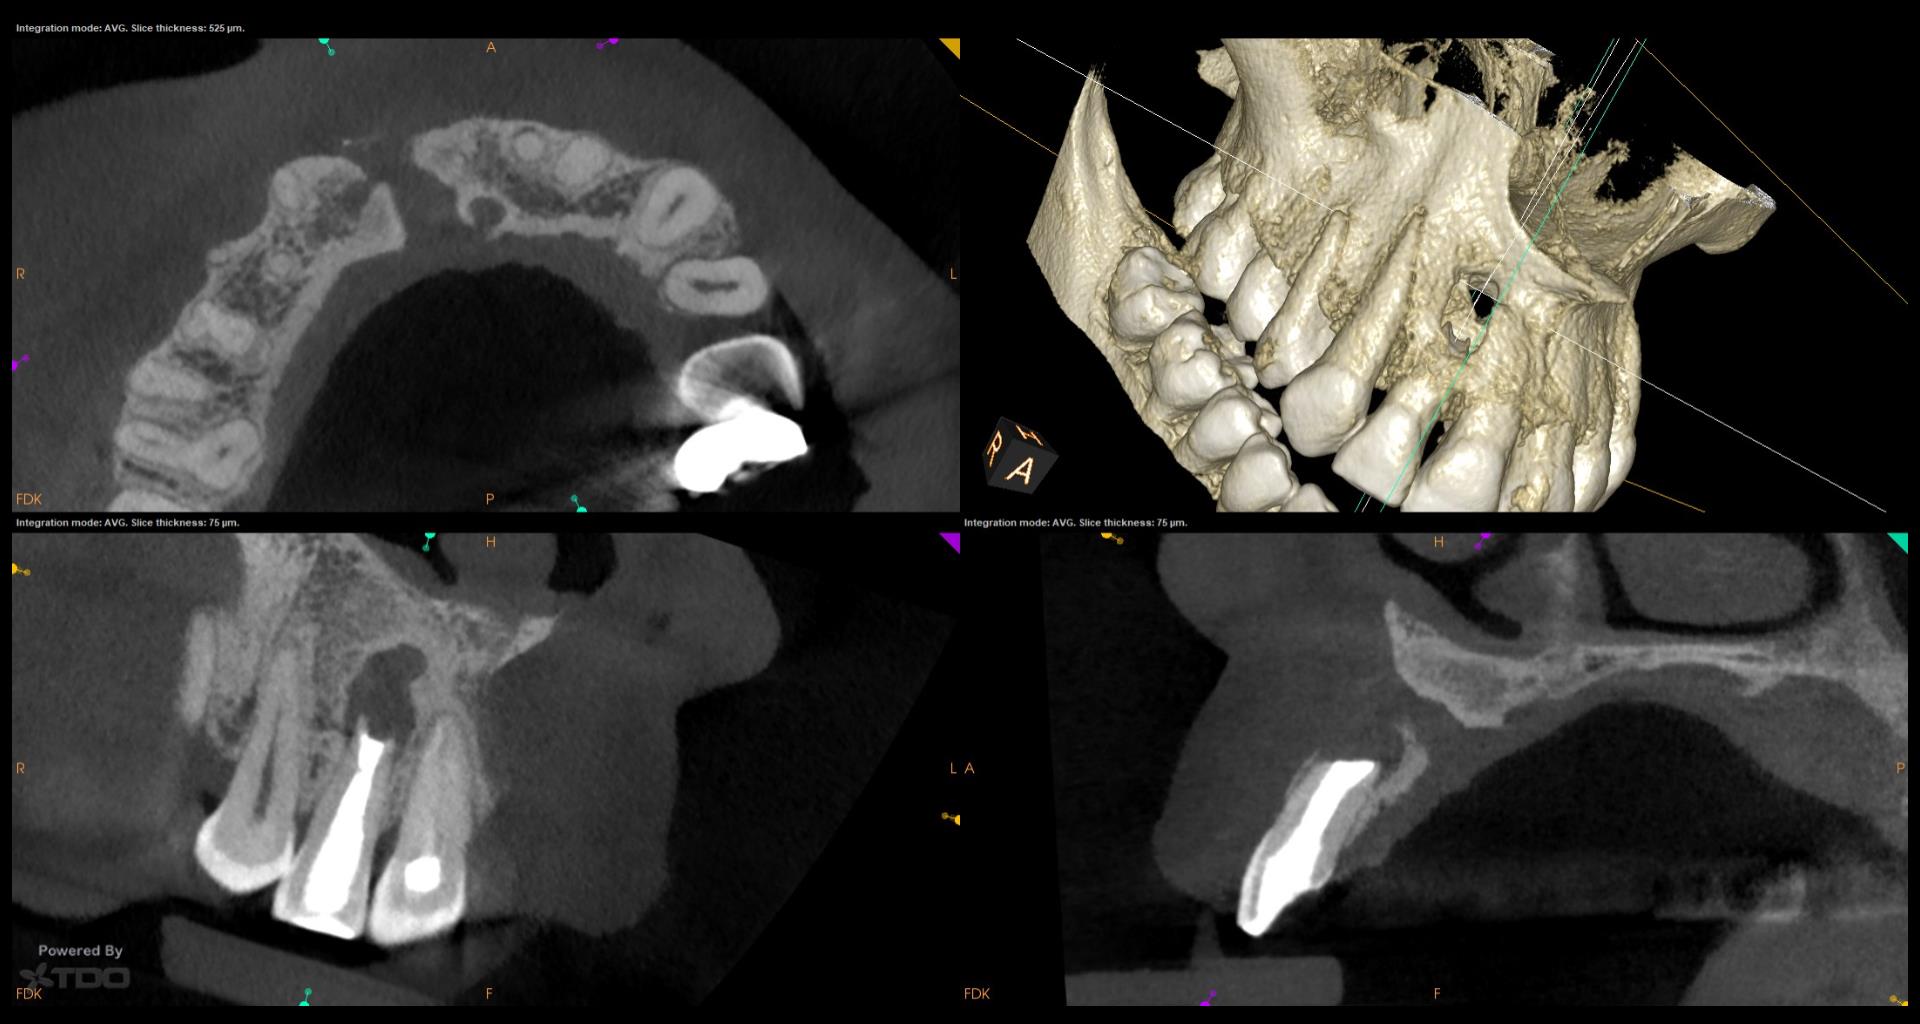

Do you have the previous review x ray s,